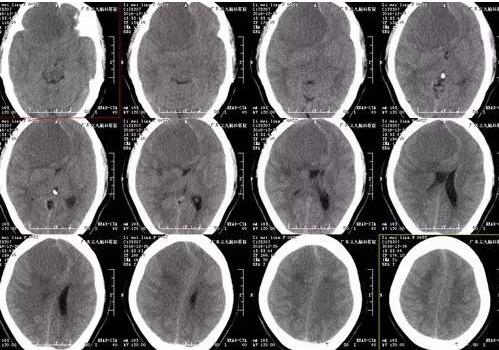

李女士,48岁,3年前开始出现间断头痛,能自行缓解,近20天头痛加重无法忍受,遂来我院门诊就诊,CT提示右侧额部类圆形稍低密度影,入院后完善检查,MR示右侧额部镰窦旁旁巨大脑膜瘤,病灶大小约7.0cm*5.9cm*6.4cm,CTA提示肿瘤周围血管包绕,血供丰富。患者手术由神经外一科主任张良主刀完成,行全麻下右侧额部镰窦旁巨大脑膜瘤切除术,术后患者症状消失,目前恢复良好出院。

脑膜瘤是颅内最常见的良性肿瘤,一般将最大径大于7.0cm的脑膜瘤称为巨大脑膜瘤。手术是治疗颅内巨大脑膜瘤的最佳方法,应争取做根治性全切除手术,以减少复发。巨大脑膜瘤血供丰富,常与颅神经、大动脉、海绵窦等粘连,或侵犯静脉窦等,手术难度大,风险高,致死致残率高。本例患者病变与大脑镰窦关系稍密切,病灶大小约7.0cm*5.9cm*6.4cm,其内示多发小血管穿行;病灶局部突入额部板障内,病变范围颅骨变薄,板障血供丰富,术中去除颅骨时出血较多。术中应用显微操作,仔细分离肿瘤周围的大脑前动脉,保护嗅神经,尽量减少了脑组织不必要的牵拉。由于肿瘤浸润矢状窦,手术时切除累及的矢状窦和大脑镰,做到肿瘤一级切除。术后患者一般情况良好,密切监测颅内压力变化及病情变化,术后有一过性发热,未有明确神经功能障碍及并发症,恢复良好出院。